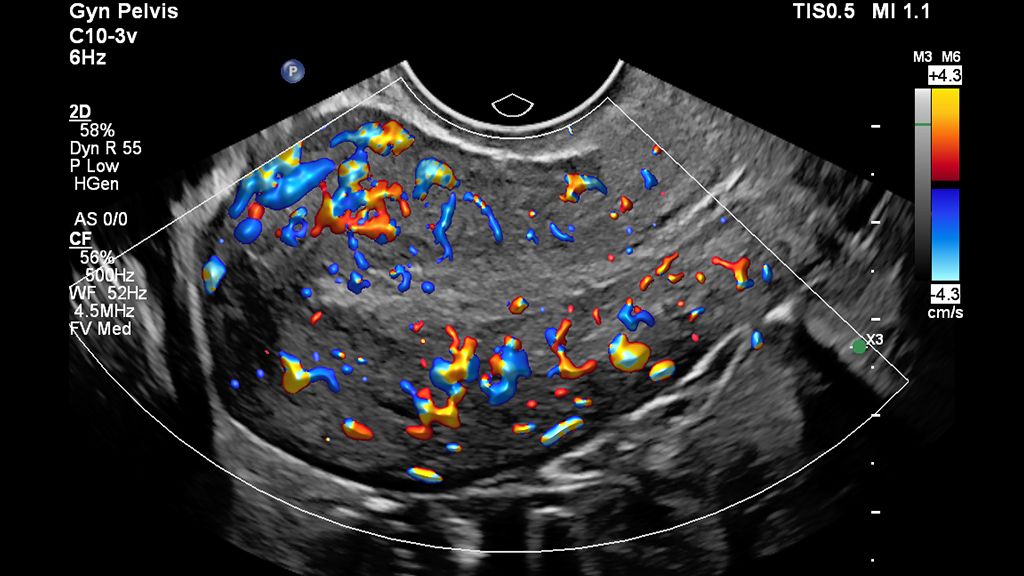

• Clinical Color Flow image of ovary scanned with Flow Viewer on EPIQ Elite

Color Flow with Flow Viewer image of the ovary